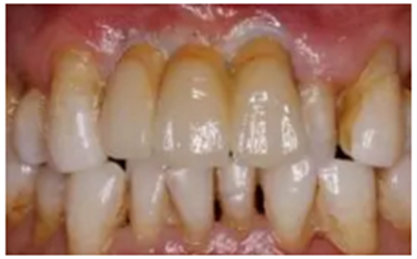

(7)修復(fù)6個(gè)月后復(fù)查

結(jié)合PRF的位點(diǎn)保存術(shù)后牙槽嵴輪廓豐滿,CBCT示骨量充足,數(shù)字化種植外科導(dǎo)板輔助下植體植入三維位置精確,種植體骨結(jié)合良好,數(shù)字化口掃系統(tǒng)數(shù)據(jù)采集高效、精確,臨時(shí)修復(fù)體戴入,軟組織成形,最終修復(fù)體戴入后穩(wěn)定、密合,牙齦軟組織色澤形態(tài)正常,美學(xué)效果良好。